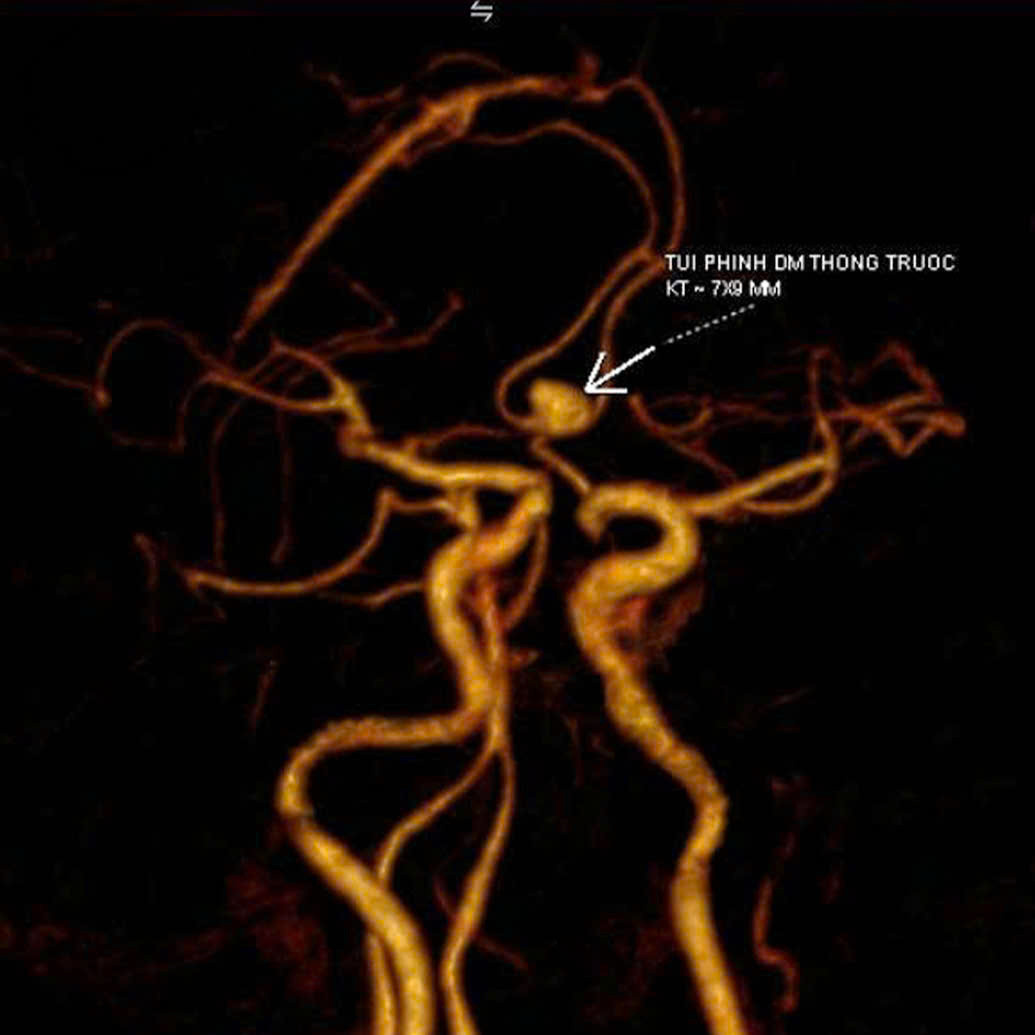

TS.BS Nguyễn Đức Anh (Trưởng khoa Ngoại Thần kinh - Cột sống) chỉ định chụp CT mạch máu não. Kết quả phát hiện túi phình kích thước 7×9mm tại đoạn động mạch thông trước, cổ rộng, vị trí có nguy cơ vỡ rất cao, dễ gây xuất huyết não và đột quỵ nguy hiểm.